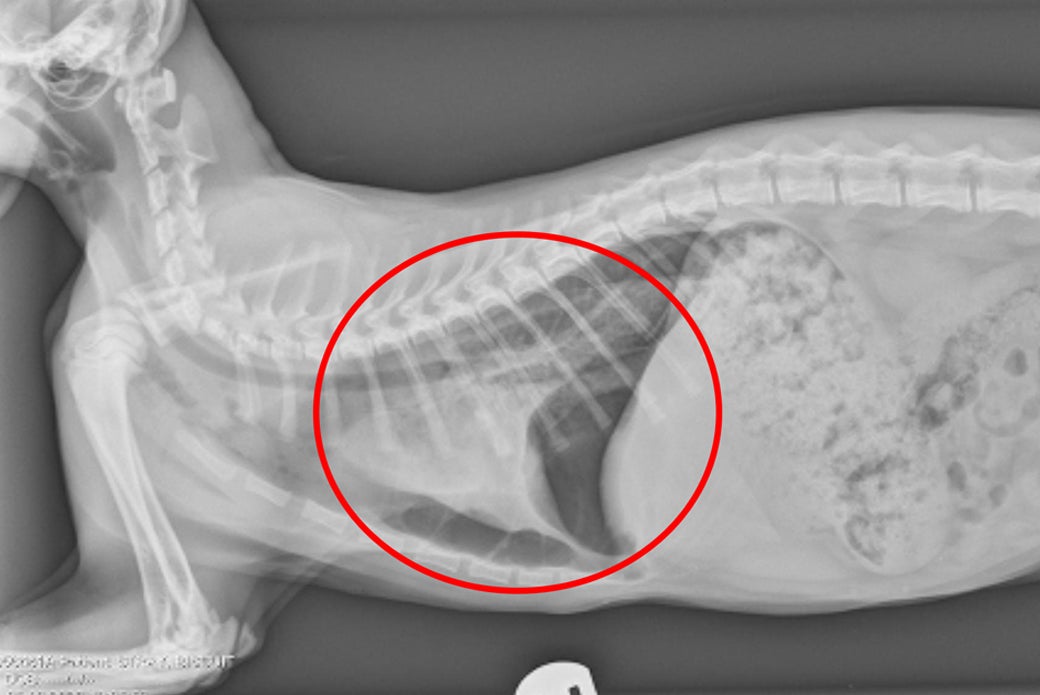

“Radiographs revealed a collapsed lung, a broken right femur, a jaw fracture and fractured metacarpals [foot bones] on both front limbs,” says Dr. Reilly.

Biscuit had a punctured lung and underwent an emergency thoracocentesis, in which free air in the chest cavity is removed so that his lungs could expand properly to allow more normal breathing. Vet staff also splinted both of his front limbs and gave him a blood transfusion after discovering he was severely anemic. For two days, Biscuit received oxygen, and stayed on pain support until he was stable enough for surgery.